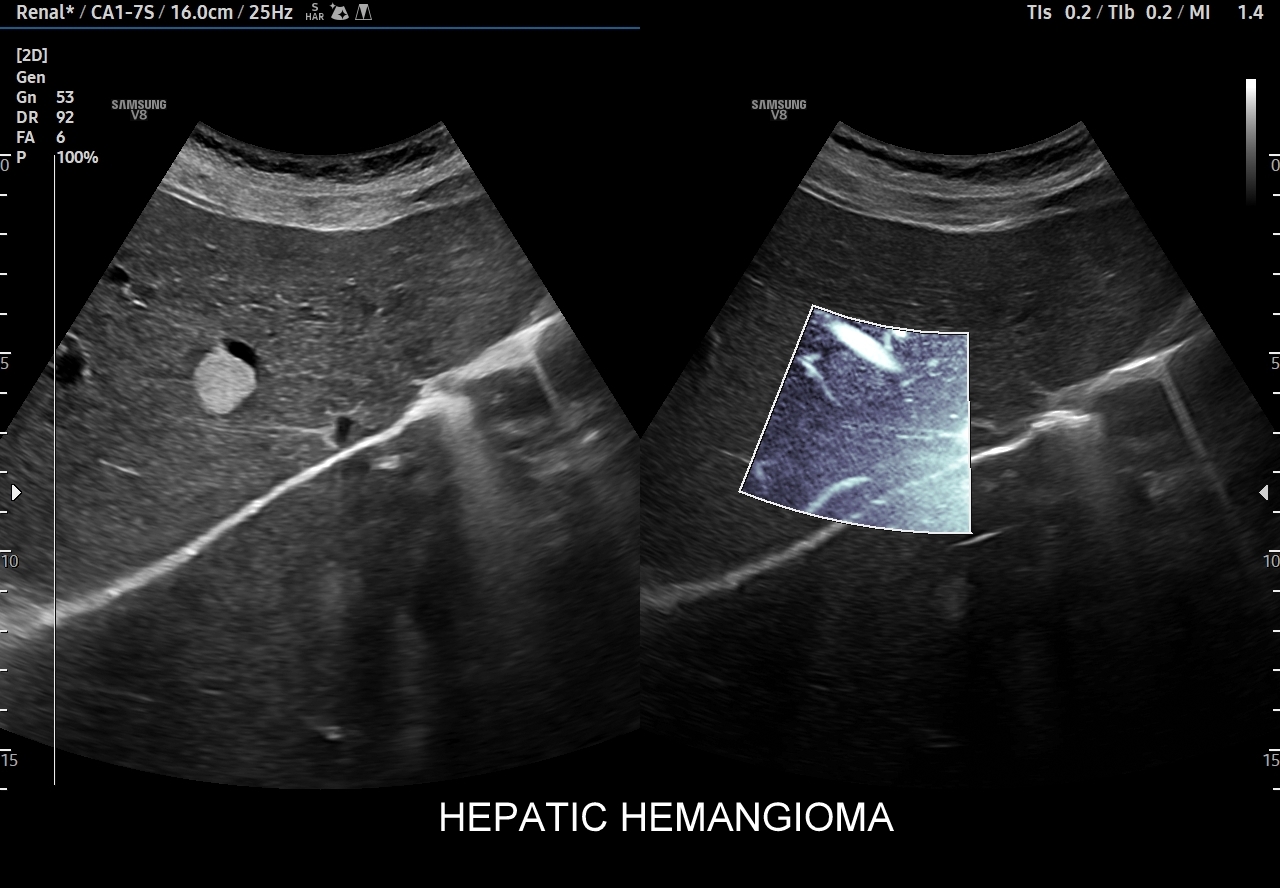

W badaniu USG w prezentacji B w niestłuszczonej wątrobie typowy naczyniak włośniczkowy lokalizuje się w pobliżu gałęzi żyły wątrobowej, a prezentuje się jako ostrookonturowana, hyperechogenna, jednorodna, krągła lub owalna zmiana ogniskowa. Ze względu na niską prędkość przepływu krwi i wynikające z tego ograniczenie detekcji w trybie color-Doppler w naczyniaku nie rejestruje się sygnału. Z kolei w trybie mikrounaczynienia (MVI / MVF) w zależności od czułości aparatury w naczyniaku można zaobserwować delikatny sygnał w postaci „poprószonego śniegu”.

Naczyniaki duże, tj. powyżej 2-3 cm, mogą mieć strukturę niejednorodną echogenicznie, w tym obszary hypoechogenne. Spotyka się także naczyniaki o charakterystyce normo- lub hypechogenicznej, w szczególności w wątrobie stłuszczonej. Z powyższych względów należy mieć na uwadze i zapamiętać, że badanie USG w podstawowym trybie B nie jest wystarczające do postawienia rozpoznania naczyniaka wątroby. W ramach obrazowej diagnostyki różnicowej najbardziej pomocnym jest badanie USG z kontrastem (CEUS), w którym to naczyniak wątroby posiada charakterystyczny wzorzec wypełnienia.